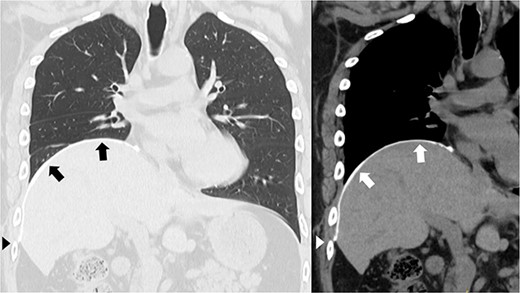

A 41-year-old man was referred to our hospital because of chest pain. Chest computed tomography (CT) revealed an anterior mediastinal tumor, and it was resected by median sternotomy. Pathological diagnosis was thymic cyst. Postoperatively, the patient developed right phrenic nerve palsy due to intraoperative stretch of the nerve and dyspnea on effort. After a year, the phrenic nerve palsy didn’t improve. He then underwent diaphragmatic plication by a right mini-thoracotomy. The elevated diaphragm was resected using an endostapler (Powered Echelon Flex®, black and green cartridges) without any reinforcement. After the second surgery, the surgical stump left by the endostapler ruptured, resulting in diaphragmatic rupture and defect. Chest CT revealed a large diaphragmatic defect (arrowhead) and prolapse of the liver into the thoracic cavity (Fig. 1). However, this condition had been misdiagnosed as the recurrence of diaphragmatic elevation for a year. His dyspnea increased in the supine position, and pulmonary function testing revealed restrictive ventilatory impairment, which led the correct diagnosis of diaphragmatic rupture. The vital capacity (VC) and %VC were 1.86 L and 39.8%, respectively. A year after the second surgery, we then repaired the diaphragmatic defect by right thoracotomy. The surgical view of the thoracic cavity showed that the liver had prolapsed from the large diaphragmatic defect, which measured 15 cm (Fig. 2). Severe adhesion was present between the liver and the edge of the torn diaphragm including the torn staple line and was carefully dissected. The diaphragmatic defect was closed with a 1 mm thick PTFE patch. Moreover, the diaphragm was reconstructed using a second 1 mm thick PTFE patch above the original placement, overlaying the diaphragmatic defect that had been closed by the first PTFE patch (Fig. 3, arrow). The second PTFE patch was fixed to the lower ribs by non-absorbable suture (Fig. 3, arrowhead). The operating time was 325 min, and the blood loss volume was 50 mL. The postoperative course was favorable, and the patient was discharged 7 days after surgery. Three months after the third surgery, his symptoms improved, and pulmonary function testing revealed that the VC and %VC were 2.24 L and 48.1%, respectively. Postoperative chest computed tomography revealed PTFE patch maintained a good position (Fig. 3).

Chest computed tomography showing that the liver had prolapsed into the thoracic cavity. (A) Coronal view. (B) Sagittal view. The arrowhead indicates the edge of the torn diaphragm, including the torn staple line.